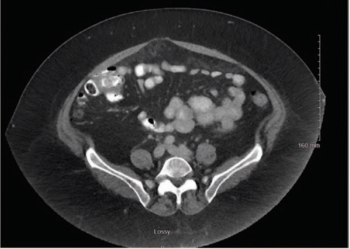

ABSTRACT Gastrointestinal stromal tumors (GISTs) are rare neoplasms of the gastrointestinal tract. They commonly present with nonspecific symptoms and thus are often discovered incidentally. They are best identified by CT scan and most stain positive for CD117 (C-Kit), CD34, and/or DOG-1. Several risk stratification classification systems have been developed based on tumor size, mitotic rate, location, and perforation. Traditional chemotherapy and radiation therapy have been very ineffective, making surgery the mainstay of treatment. The discovery of mutations associated with these tumors has revolutionized the treatment approach. Imatinib mesylate, a selective tyrosine kinase receptor inhibitor, used as adjuvant or neoadjuvant therapy, has greatly improved the morbidity and mortality associated with GISTs. As the survival of patients has increased with the long-term use of targeted therapies, quality-of-life issues now have become much more relevant and have come to the forefront of care. We present a young woman who was successfully treated for GIST but now faces associated long-term adverse effects of imatinib, including the challenge of preserving fertility and the potential for childbearing.